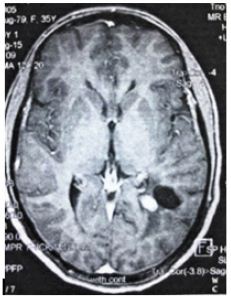

We report here a case of a desmoplastic non-infantile ganglioglioma (DNIG) in a 35 year old woman. The tumor was identified incidentally during the staging procedure for a multifocal papillary thyroid carcinoma. In the recent medical history of the patient there were no neurological signs and symptoms. Apart from the absence of a definite clinical picture, even the localization of the present tumor is considered uncommon. The performed MRI showed a neoplasm measuring 1.4 cm in its maximal diameter, which was almost adherent to the choroid plexus of the left ventricular trigonum. The tumor consisted of both a solid and a cystic component, with the former showing contrast enhancement after gadolinium administration (Figure 1). Subsequently, during the neurosurgical procedure, the tumor was carefully detached from the choroid plexus and completely excised; a fact that was confirmed by post-surgical computed tomography.

Figure 1: A tumor mass composed of a solid and a cystic component, localized to the left ventricular trigonum. Contrast enhancement of the solid portion after gadolinium administration